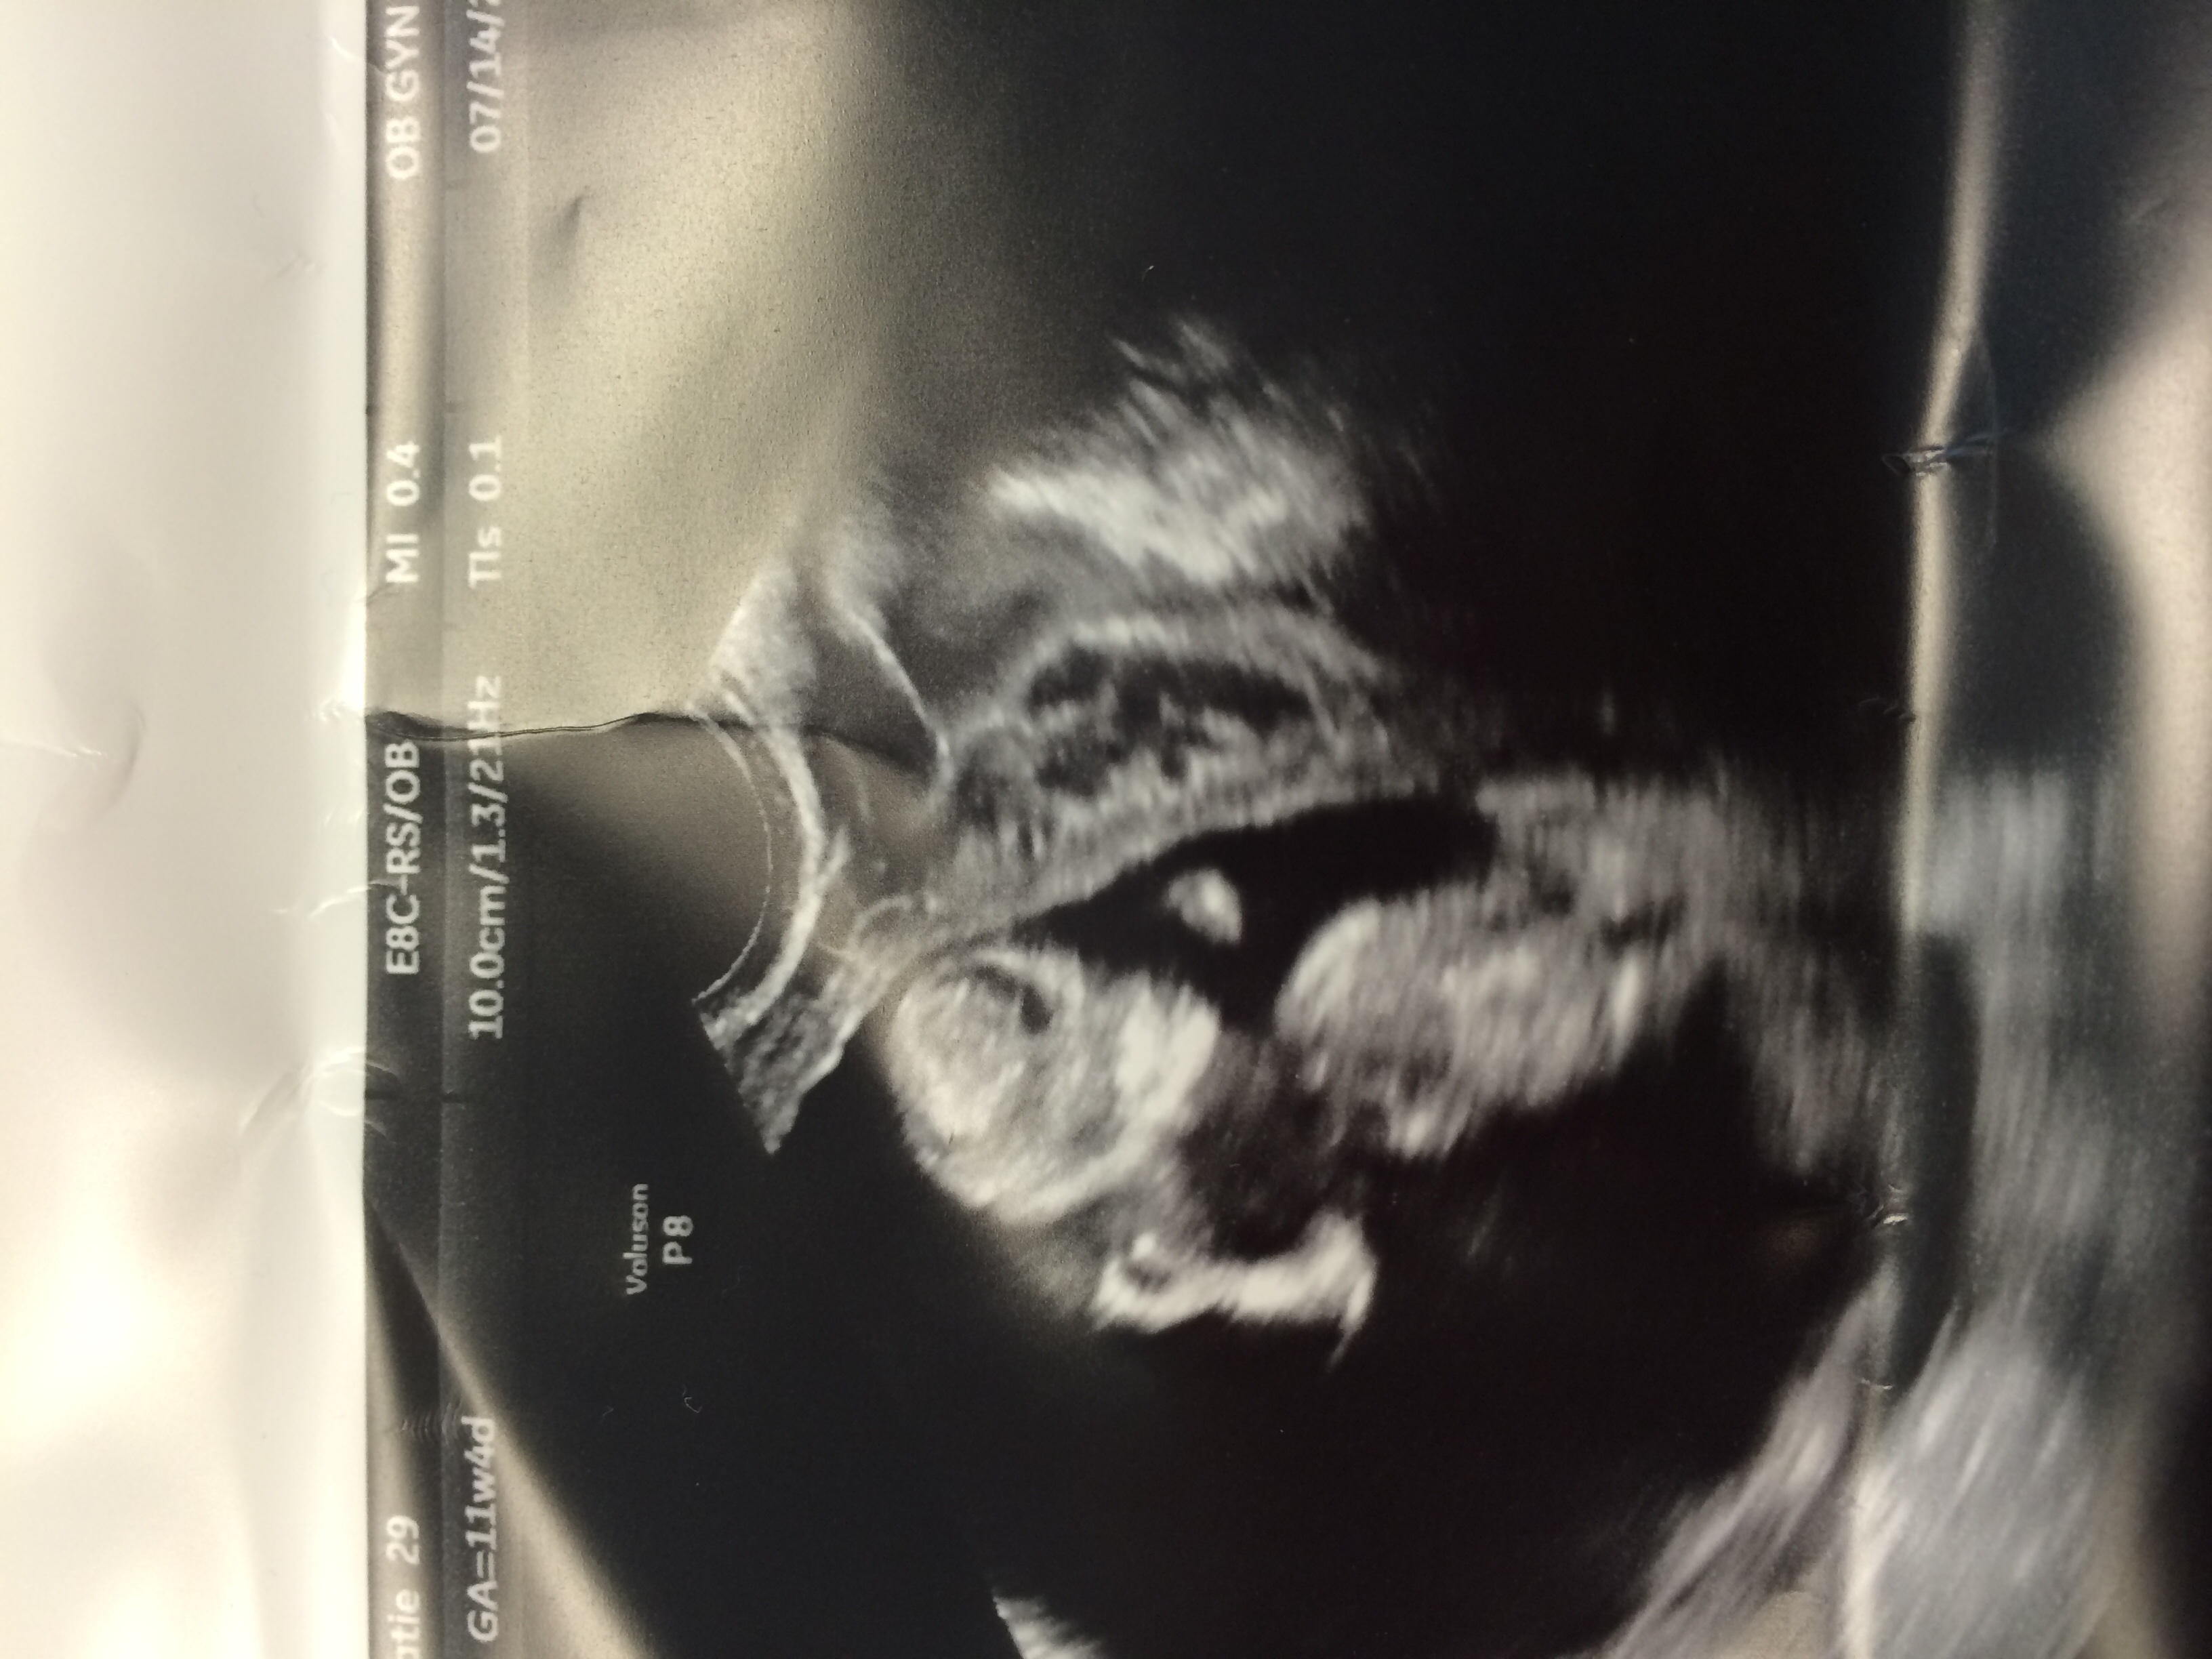

I had a checkup today after a week of spotting and stretchy cramps... And doc said everything looked great! HR 164, baby was wiggling all around and doc mentioned we had a very photogenic and active baby:)

image.jpg